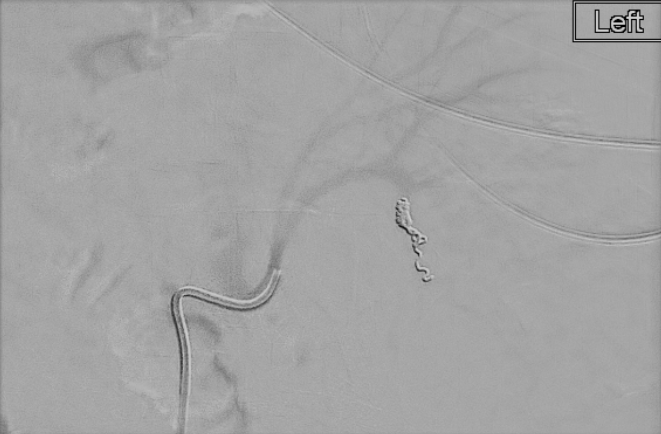

58 year old cirrhotic patient, underwent renal biopsy at outside facility. 1 day of progressive abdominal pain. CT with active bleeding from biopsied kidney.

#IRad quick to#embolize the vessel and#stopthebleed#MIIP#InnovationToHeal#Radiology#TwittIR#IRadRes pic.twitter.com/8GcA0rVLtE